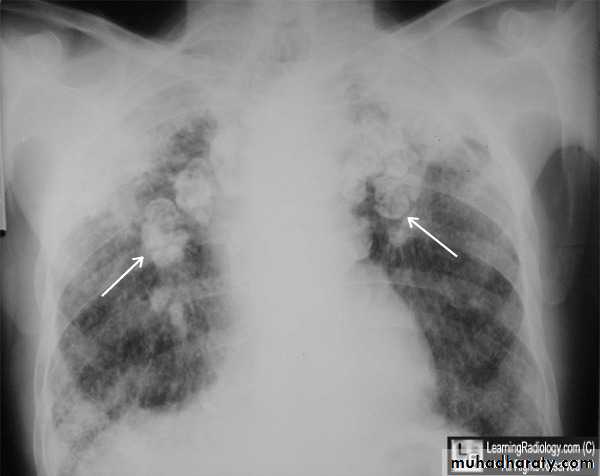

2-Complicated pneumoconiosis; large dense masses appear mainly in the upper lobes (also known as progressive massive fibrosis, PMF). Presented as cough, production of sputum, that may be black (melanoptysis) and breathlessness. Respiratory failure after cessation of exposure and right ventricular failure.

3-Caplan's syndrome describes the coexistence of rheumatoid arthritis and rounded fibrotic nodules 0.5-5 cm in diameter.

The clinical and radiological features are similar to those of coal worker's pneumoconiosis, with multiple well circumscribed 3–5-mm nodular opacities, predominantly in the mid- and upper zones

Enlargment of the hilar glands with an 'egg-shell' pattern of calcification is characterestic.